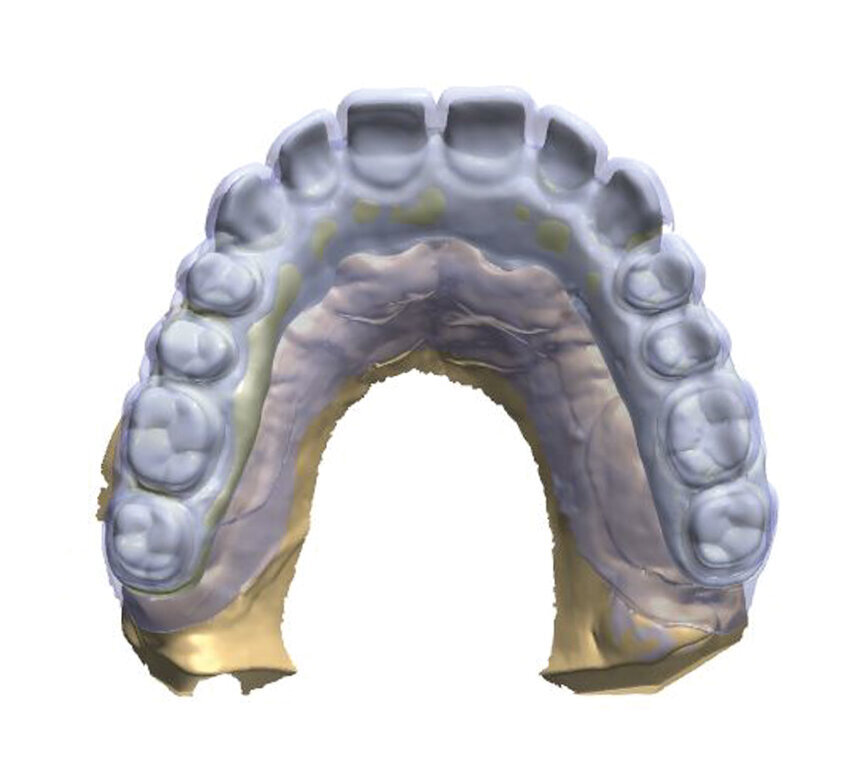

Fig. 1: A virtual image of a scanned model with abutments and telescopic crowns.

In order to prepare the bridge, a model was scanned and transferred onto a computer using software to design the bar (Fig. 1). The bar was designed by using special software in such a way that the whole design was transparent in the first phase so that the location of abutments and the position of the telescopic abutments at the frontal section could be visible (Fig. 2).